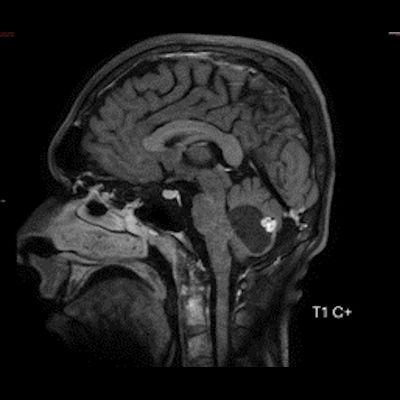

- B) Beyin MRG incelemesinde; 4. ventriküle bası etkisi oluşturan yaklaşık 3.5 cm boyutta, T2A hiperintens T1A hipointens kistik komponent (oklar) ve posteriorunda T1 ve T2A serilerde parankim ile izointens, içerisinde flow void alanların (oklar) izlendiği, post kontrast görüntülerde yoğun kontrast tutulumu gösteren mural nodül (oklar) barındıran düzgün sınırlı lezyon izlenmektedir.

- Kontrastlı incelemelerde mural nodül belirgin ve yoğun kontrast tutulumu gösterir. Ancak kist duvarında genellikle kontrastlanma beklenmez.

- T1 ve T2A görüntülerde flow voidler sıktır.